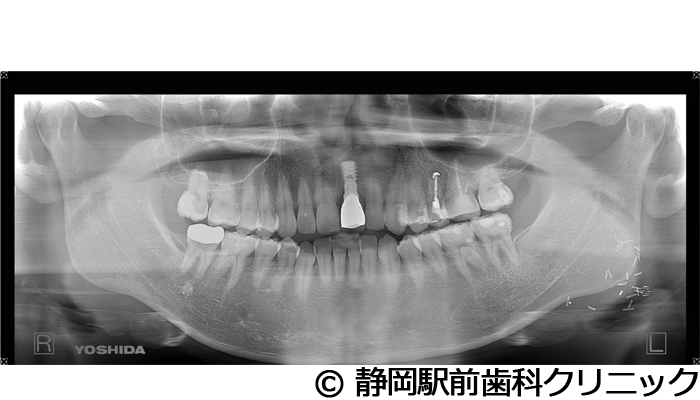

【症例5】全顎的インプラントとセラミックによる審美補綴

- 治療前

- 治療後

- 治療名

- 全顎的インプラントとセラミックによる審美補綴

- 費用

- 1,800,000円(税込)

- 期間

- 1年6ヵ月

治療内容

患者様の症状

全体的に歯がないため、噛めない。インプラント治療希望。

治療方法

全体的に残根は抜歯を行い、術前にCTを撮影し緻密に治療計画を立てた。インプラント埋入はブロックごとに行い、噛み合わせの調整を重ねた後、人工歯を被せて咬合と審美の回復を行いました。

治療結果

しっかり奥歯で食べ物を噛み切ることができるようになり、何でも食べることができるようになったと喜んでいただくことができました。口元を気にせずに笑うこともできるようになり、見た目もキレイになったとご満足いただけました。

※治療結果は個人差があります。

治療を行う上での注意点(リスク・副作用)

術後は、出血、腫れ、痛みなどが出る可能性があります。